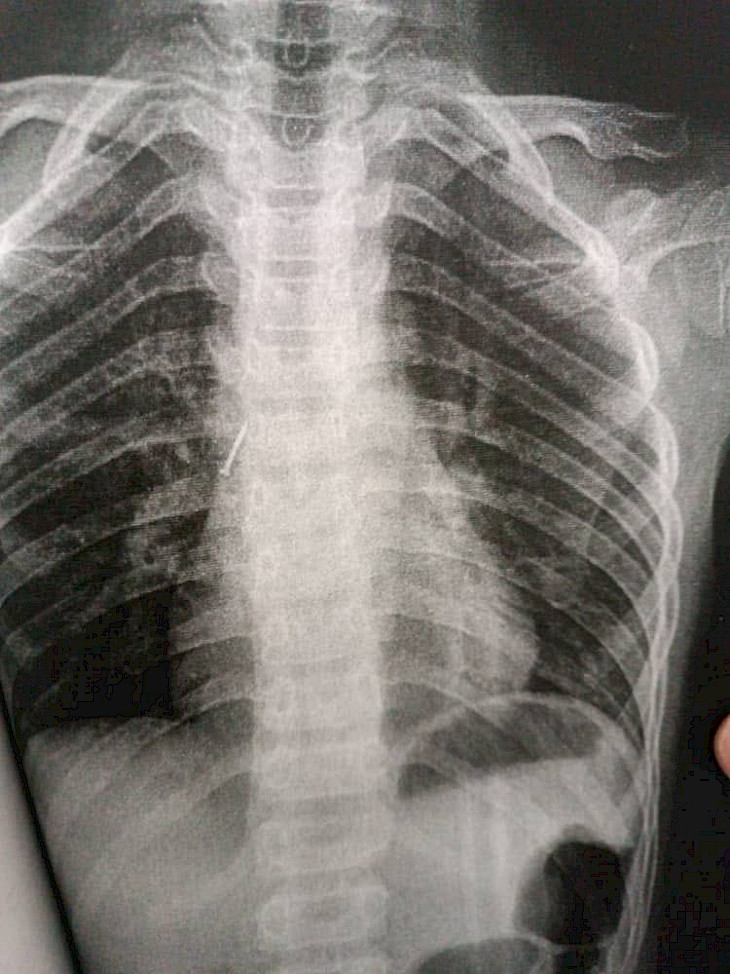

Бишкек, 08.08.23. /Кабар/. Кечээ, 7-августта Ош облустар аралык балдар клиникалык ооруканасына учтуу зат жутуп алган 10 жаштагы бала түшкөн. Бул тууралуу оорукананын басма сөз кызматынан билдиришти.

Маалыматка ылайык, бала оң өпкөсүнөн жабыркап, канцелярдык мык бронхага сайылып калган. Дарыгерлер тарабынан оор абалдагы балага тезинен жардам көрсөтүлүп, бала аман калды.